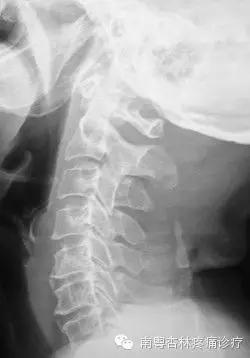

通过X线片上的颈椎显像:沿此曲度走行,在各个颈椎椎体后缘都有形成的连续、光滑的弧形曲线,医学上称之为颈椎曲度。当长时间不正确的坐姿、或是长时间的劳累、颈椎缺少活动、脊柱损伤、脊柱钙化等就会导致颈椎生理曲度变直。

生理曲度存在